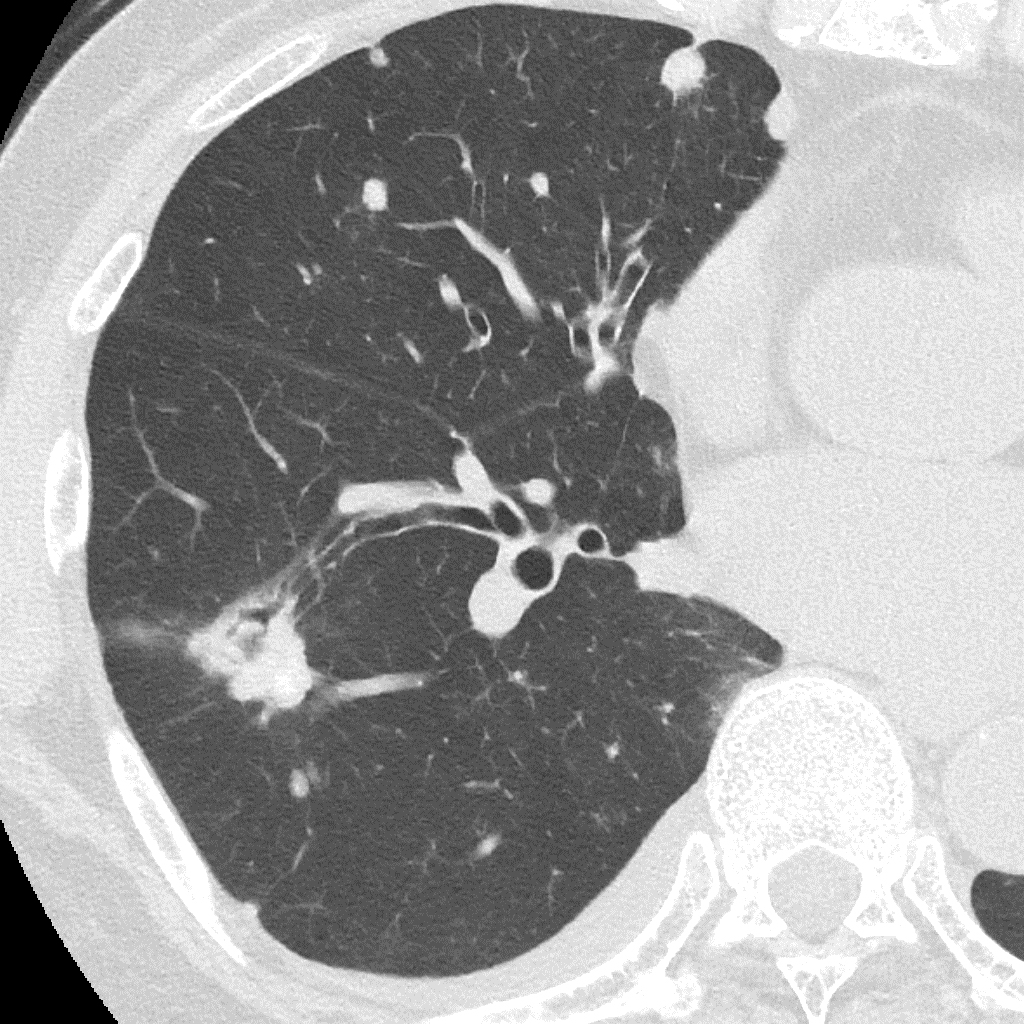

Порівняння звичайної роздільної здатності з ультрависокою роздільною здатністю (УРЗ)²

КТ з ультрависокою роздільною здатністю 0,25 мм ³